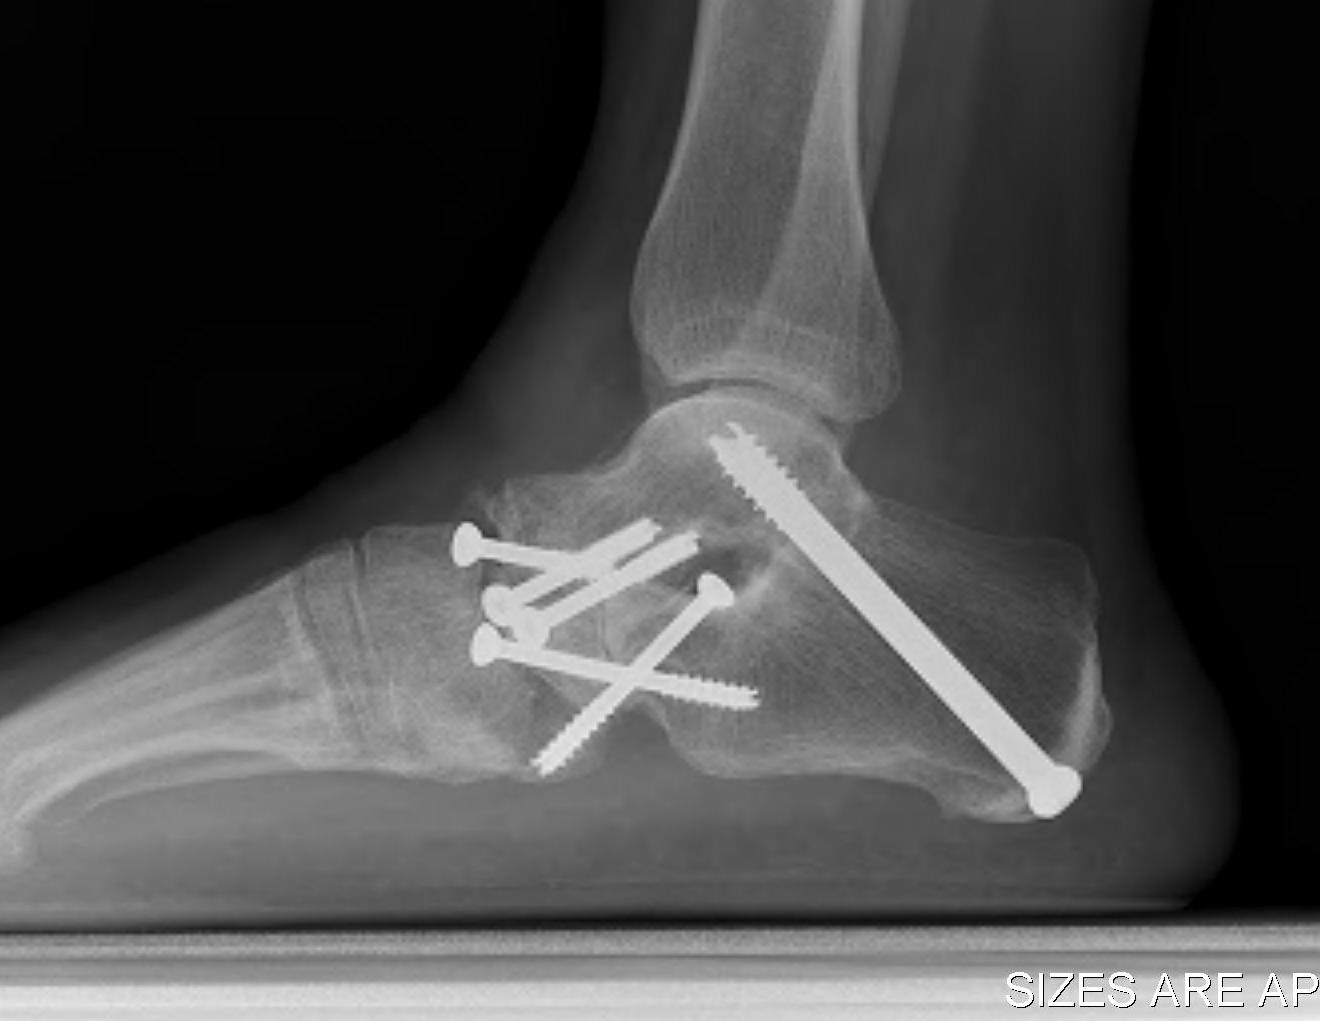

Fixation

- TJN screws

- CCJ screws +/- plate

- STJ screws